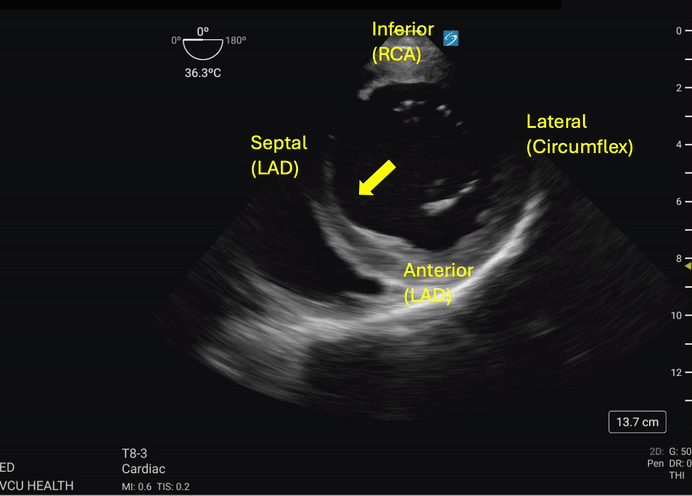

Hypokinesis or akinesis of the left ventricular myocardium segments can indicate tissue ischemia or infarction in specific vascular territories (Figures 3a and 3b). The RCA supplies the myocardium of the inferior wall of the left ventricle. On TEE, the inferior wall is located closest to the probe footprint, since the probe is coming from the stomach located inferior to the heart. The LAD supplies the myocardium of the anterior and septal portions of the left ventricle. The circumflex artery supplies the lateral portion of the left ventricular myocardium and will be shown on the rightward aspect of the ultrasound image.4

In the absence of regional wall motion abnormalities or other confounding factors, the operator should observe the left ventricle walls concentrically and symmetrically contracting toward the center-most aspect of the left ventricle cavity during ventricular systole. Any asymmetry during this process should raise concerns about a wall motion abnormality in one of the distributions noted above and, thereby, concerns of myocardial ischemia/infarction.

Figure 3b. The septal wall exhibits focal akinesis (arrow) in addition to global hypokinesis which may suggest an acute LAD lesion in the right clinical context. Image courtesy of Lindsay Taylor, MD.

The patient complained of chest pain just before their arrest and suffered recurrent ventricular dysrhythmia, suggestive of myocardial ischemia as a potential underlying etiology. Prolonged periods of sustained ROSC between dysrhythmias were not achievable, preventing ECG analysis. However, evaluation of the myocardium using TEE was feasible. The TG SAX view revealed a focal region of poor contractility in the anterior wall, supporting the suspicion of ischemia and localizing the distribution to the LAD.